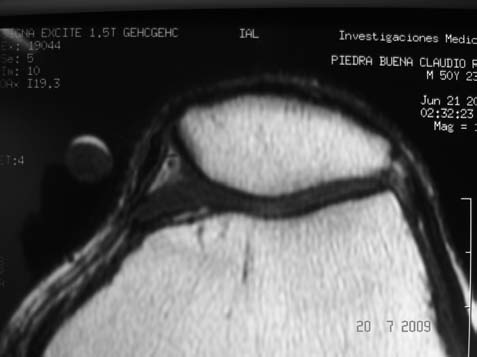

RX simple: buen eje patelofemoral, no se halló evidencia de cuerpo libre osteocondral. (Fig. 1)Resonancia magnética: se identificó una tumoración en el alerón patelar medial, circunscripta, de 7mm de diámetro, localizada en el sector parapatelar medial, a nivel del plano de sección transversal mediopatelar.T1-T2 sin y con gadolinio. (Fig. 2 A-B)

Figura 2A: Imagen axial en T1 sin contraste EV: Se observa imagen isointensa en T1, de bordes netos, que contacta al ligamento alar interno